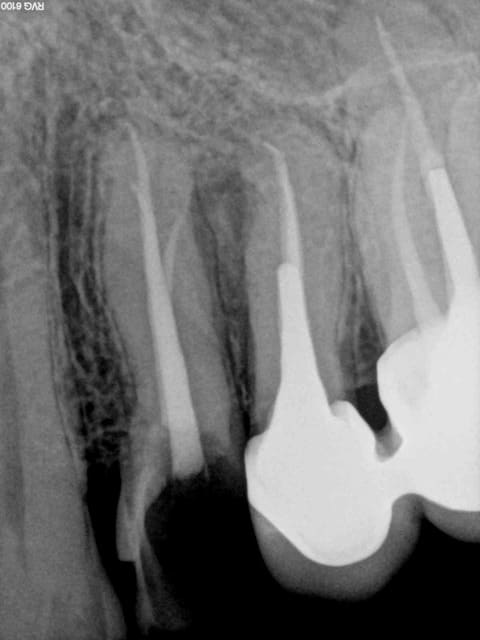

Le mv1 et le dv ont été obturés il y a 8 ans en mono cone.

En gutta chaude la différence se voit car ca n'est pas homogène à la radio comparé à un monocone scellé.